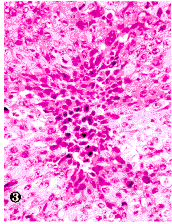

图3 CNE-2裸鼠移植瘤“皱缩性坏死”灶(×50)

Fig.3 Afocus of“shrinkage necrosis”in H&E stained slide of CEN-2 nude mice transplant

The neoplastic cells of“shrinkage necrosis”had eosinophilic cytoplasm and pyknotic nucleus(×50)

CNE-1移植瘤分化较好,在HE染色下细胞分界较清楚,有时可见细胞间桥和个别角化细胞(插页1图1),而CNE-2移植瘤则分化较差,细胞分界不清楚,无细胞间桥和个别角化细胞(插页1图2)。CNE-1及CNE-2各代裸鼠移植瘤组织在HE染色下均可见到多灶性肿瘤细胞死亡。细胞死亡灶中有“皱缩性坏死”(“shrinkage necrosis”)和凝固性坏死两种形态,而常以“皱缩性坏死”为主(插页1图3)。“皱缩性坏死”的细胞相互分离,体积缩小,胞浆高度嗜酸性,内含1~2个固缩而深染的核,少数细胞甚至不含核(插页1图3)。在TUNEL染色下,这些“皱缩性坏死”的细胞呈强阳性的末端标记信号。凝固性坏死细胞轮廓尚存,胞浆染色较浅,核已消失(插页1图3)。在所谓非细胞死亡灶的HE染色下仍可见到少数位于细胞间和被瘤细胞吞噬的凋亡小体(插页1图2)。凋亡小体表现为不含或含染色质的微小嗜酸性小体,被吞噬在细胞内的凋亡小体旁常有一个空晕。在TUNEL染色下除了这些凋亡小体呈阳性信号外,许多HE染色下被忽视的凋亡小体都可被检测到(插页1图4)。每个高倍视野(10×40)至少有100个凋亡小体信号。